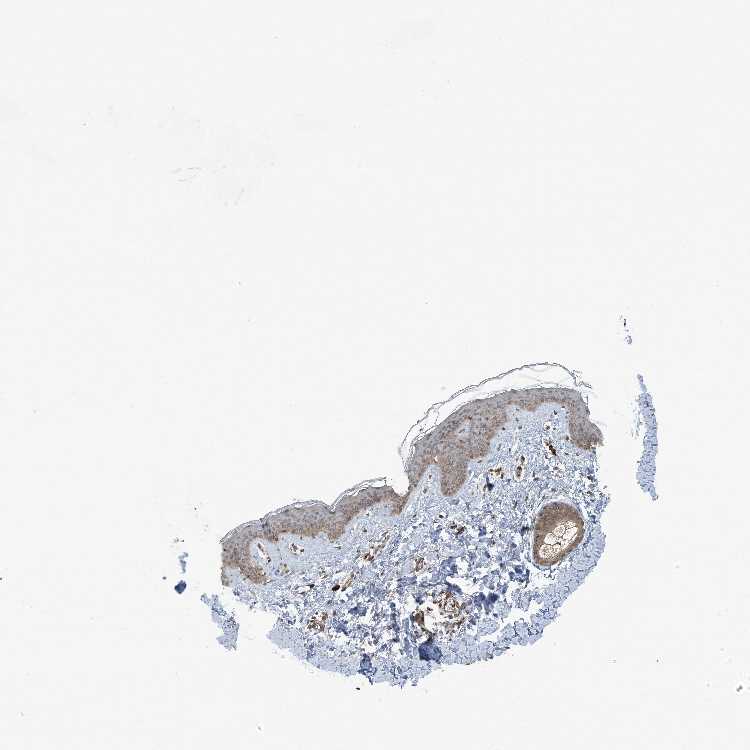

TISSUE PRIMARY DATA SKIN Show tissue menu

SKIN 1 - Antibody stainingi

Antibody staining in the annotated cell types in the current human tissue is reported as not detected, low, medium, or high, based on conventional immunohistochemistry profiling in selected tissues. This score is based on the combination of the staining intensity and fraction of stained cells.

Each image is clickable and will lead to virtual microscopy that enables deeper exploration of all samples and also displays staining intensity scores, fraction scores and subcellular localization as well as patient and tissue information for each sample.

Antibody HPA035159Antibody HPA035160

Langerhans LowMedium

Fibroblasts MediumMedium

Keratinocytes LowMedium

Melanocytes MediumHigh